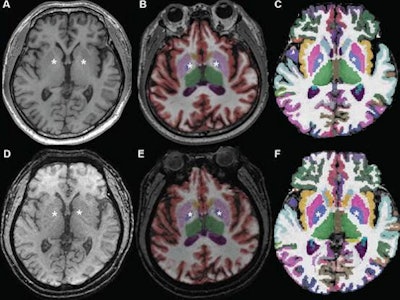

The researchers then used both the commercial NeuroQuant software application (CorTech Labs) and FreeSurfer (Harvard University) to perform automated brain segmentation. Next, they compared the measurements between sequences for nine regions in each brain hemisphere.

The patients received isotropic 3D T1-weighted imaging using an inversion recovery gradient-recalled echo (GRE) sequence at a slice thickness of 1 mm and acquisition time of 3 minutes and 4 seconds. Patients exhibiting motion also received an isotropic ultrafast 3D-EPI sequence with a slice thickness of 1.2 mm and an acquisition time of 30 seconds in the same scanning session.